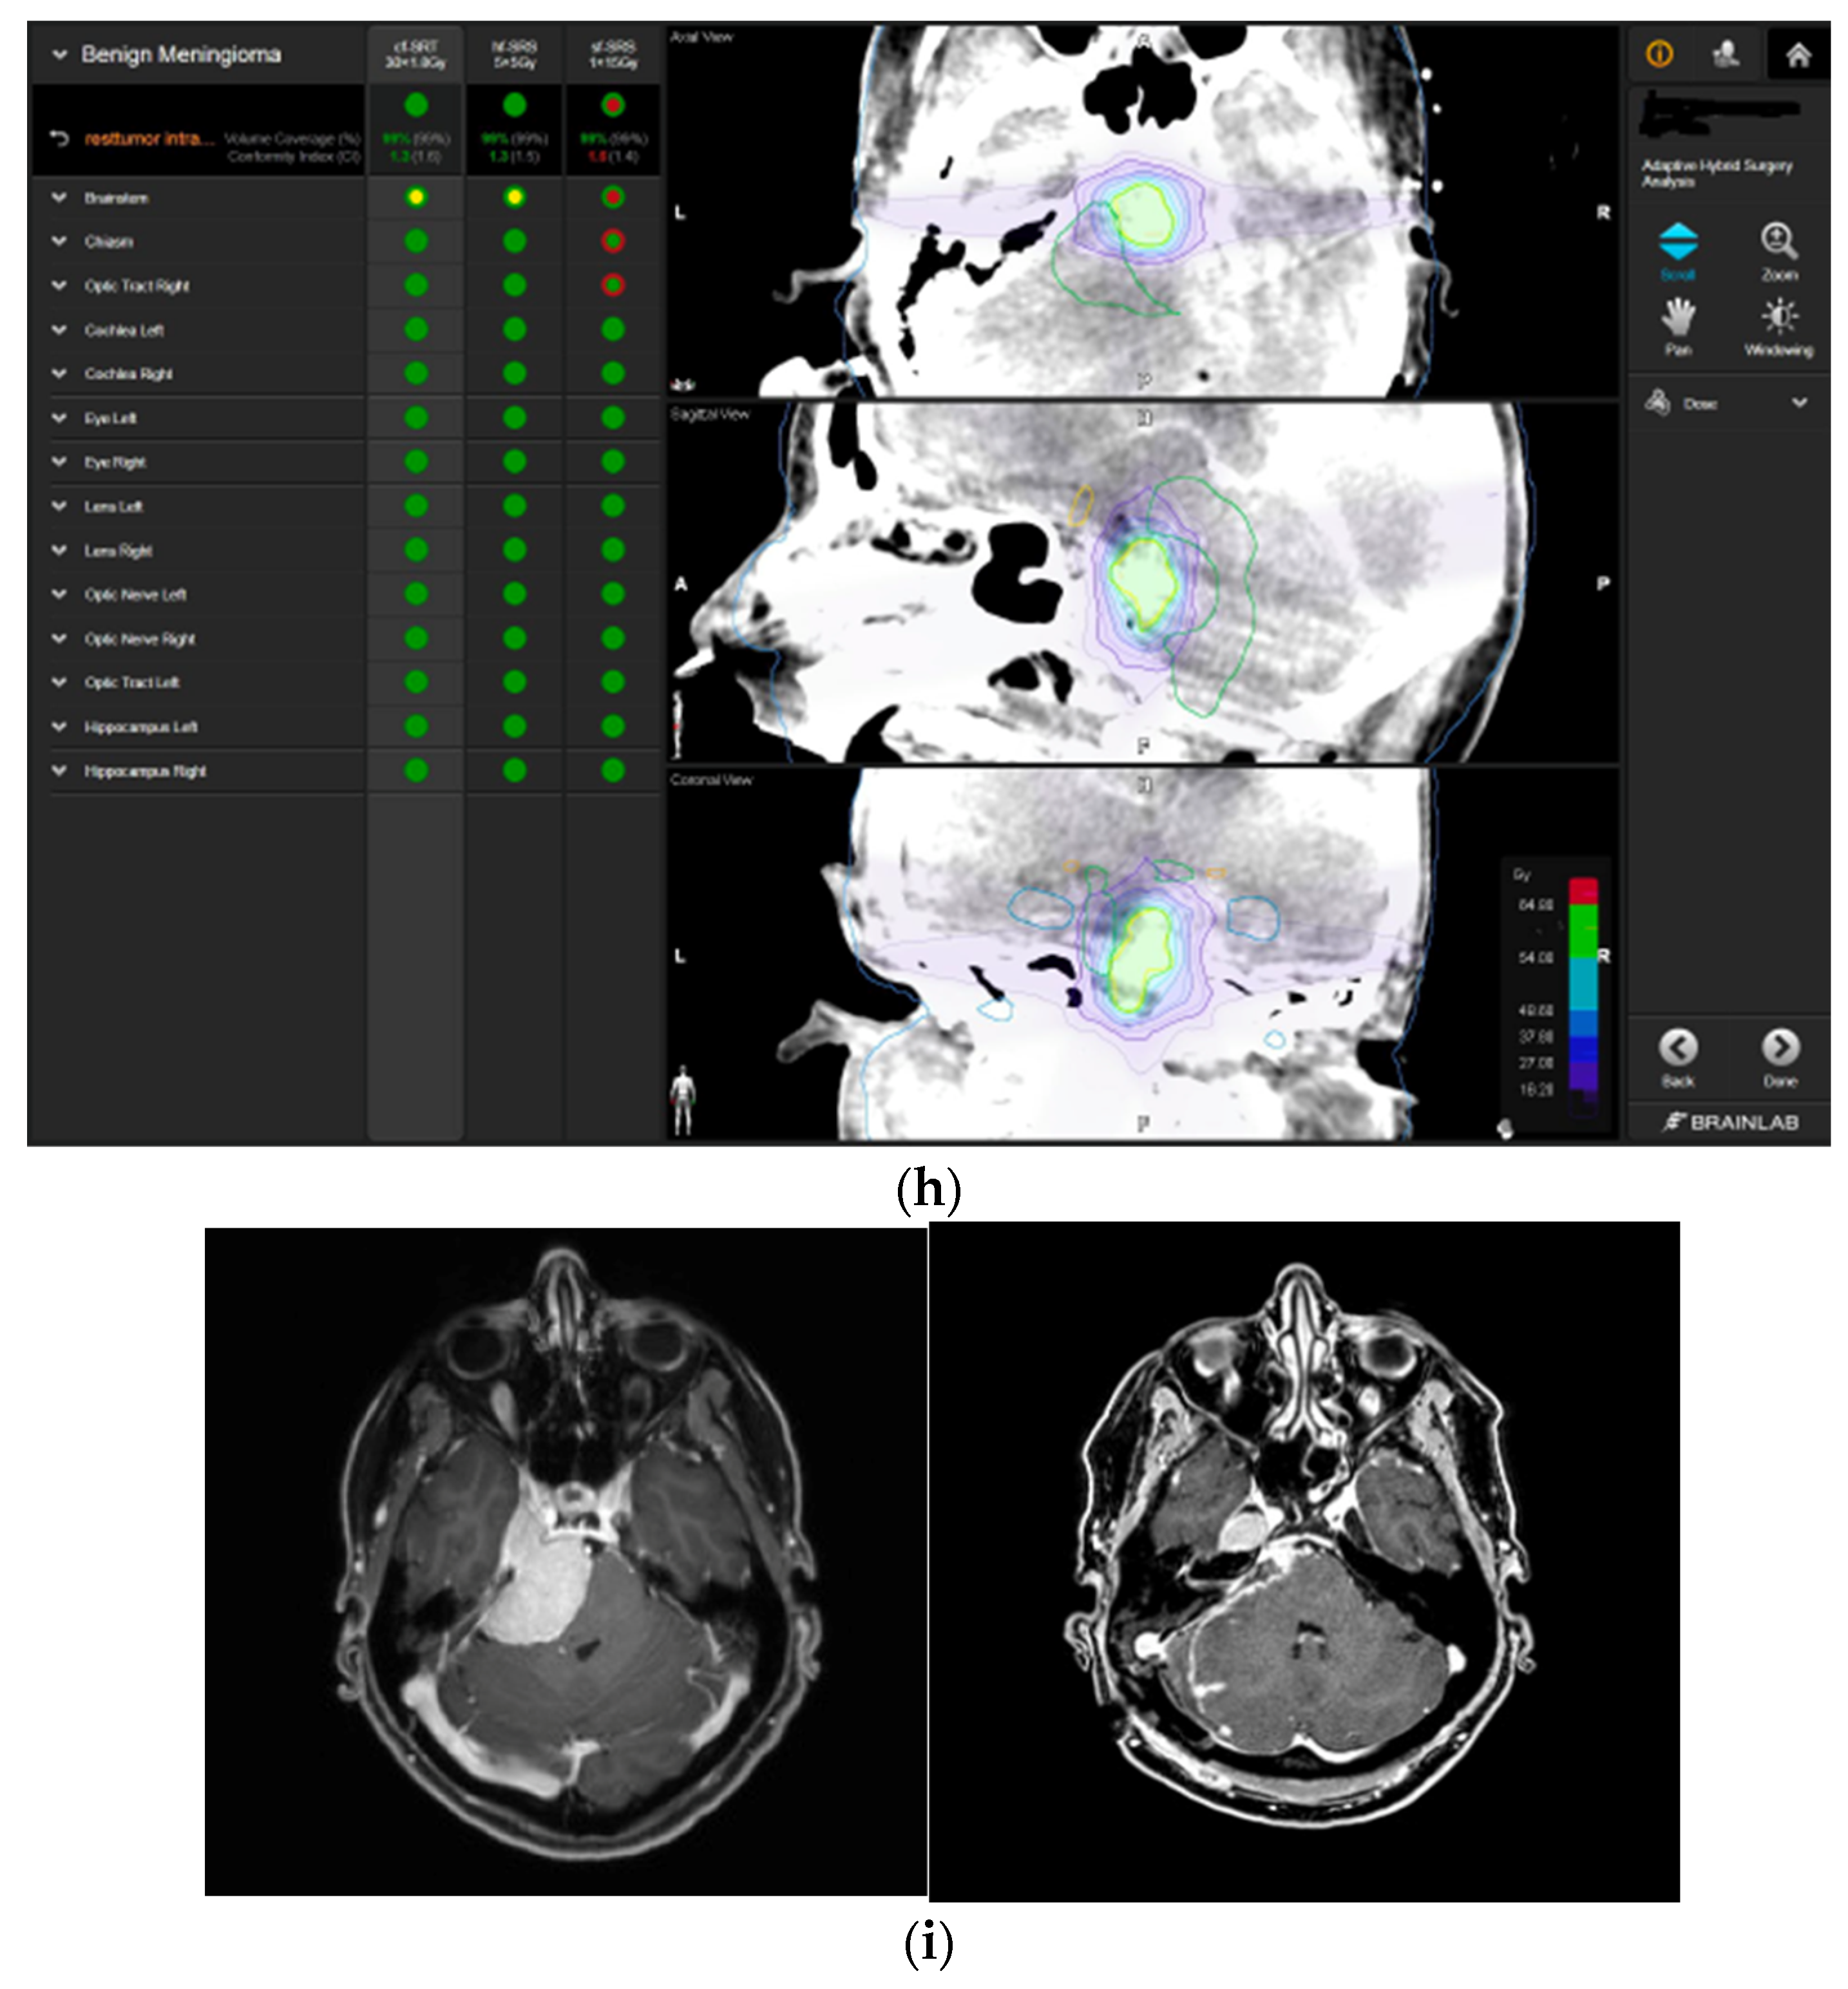

A 58-year-old female presented with progressive headache, difficulty swallowing, diplopia, hearing loss, and reduced face sensitivity on the right side (Figure 4). Elective craniotomy and AHSA-assisted tumor resection were performed. The patient underwent hypofractionated radiosurgery (5 × 5 Gy) of the residual meningioma one year after tumor resection.

Figure 4.

Second representative case of AHSA-supported tumor resection. (a) MRI imaging of petroclival meningioma (axial, coronal, sagittal). (b) Depiction of preoperative tumor volume (orange) and planned residual tumor volume (red). (c) AHSA summary table showing the stereotactic radiation constraints for the preoperatively planned residual tumor volume. With this plan, conventional fractionation and hypofractionation were feasible with effective tumor coverage.

—brainstem: mean dose is safe, while the max. dose is marginally safe;

—right optic tract: mean dose unsafe, max. dose is marginally safe;

—right hippocampus: marginally safe, and mean dose unsafe, max. dose is marginally safe. (d) First intraoperative structure update (ISU) with a residual tumor volume of 82% with the calculated dose constraints for conventional and hypofractionated radiotherapy. Single dose stereotactic radiosurgery was not feasible with this degree of remaining tumor. At this point, the dose constraints for conventional radiotherapy were:

—brainstem: mean dose is safe, max. dose is marginally safe;

—right hippocampus: mean dose unsafe, max. dose is marginally safe. Hypofractionated radiotherapy:

—brainstem: marginally safe;

—right cochlea: mean dose unsafe, max. dose safe;

—right hippocampus: mean dose unsafe, max. dose is marginally safe. (e) Second intraoperative ISU with residual tumor volume of 74% and calculated dose constraints for hypofractionated radiotherapy. Single dose stereotactic radiosurgery was still not considered feasible with this residual tumor volume. The dose constraints for organs at risk for conventional and hypofractionated radiotherapy were unchanged compared to the first ISU. (f) Third intraoperative ISU with residual tumor volume of 47% and calculated dose constraints for conventional, hypofractionated radiotherapy, and radiosurgery. The current dose constraints for organs at risk were the following for conventional radiation:

—right hippocampus: mean dose unsafe, max. dose is marginally safe. Hypofractionated radiation, which was unchanged for the first and second ISU:

—right hippocampus: mean dose unsafe, max. dose is marginally safe. For single fraction radiosurgery, the OAR dose constraints were available but considered to be unsafe.

—brainstem: mean dose unsafe, max. dose safe;

—chiasma: unsafe;

—right cochlea: unsafe;

—left optic tract: mean dose unsafe, max. dose safe;

—right optic tract: unsafe;

—right hippocampus: unsafe. (g) Overlay of preoperatively estimated and intraoperative effective residual tumor volume in AHSA. (h) Final intraoperative dose constraints after last ISU and data fusion with intraoperative CT. The dose constraints for OARs appeared to improve and were as follows for conventional and hypofractionated radiotherapy:

—brainstem: mean dose is safe, max. dose is marginally safe.

—brainstem: mean dose safe, max. dose unsafe;

—chiasm: mean dose unsafe, max. dose safe;

—right optic tract: mean dose unsafe, max. dose safe. (i) Comparison of pre- and 3 months postoperative MRI for stereotactic radiation planning. The residual tumor was finally treated with hypofractionated radiotherapy (5 × 5 Gy).